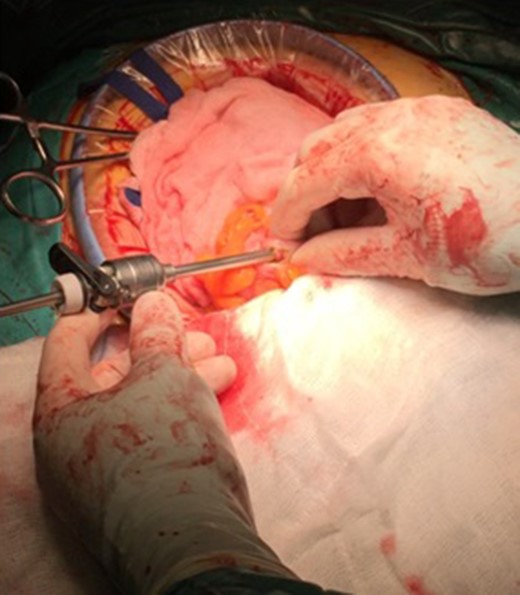

An isolation of the peritoneal cavity with compresses was initially performed. A cross-section of the peripheral truncation was performed on the colonic tape at the point where the ileocolonic anastomosis would be later created. A 10 mm laparoscopic port was inserted in the hole and CO2 insufflations started (Fig. 1). After bowel dilatation the camera was inserted through the laparoscopic port in the colon lumen. During the time the camera is intraluminal, water injection is provided, to avoid thermal injury of the mucosa. Overview of the lumen, until the splenic flexure bend and the beginning of the descending colon was performed. A hole was then applied to the colic tape at the lower third of the sigmoid (Fig. 2). Again, a 10 mm laparoscopic port was inserted and the laparoscopic camera was used to inspect the bowel lumen up to the splenic flexure. After the endoscopic inspection of the bowel has been completed, the laparoscopic ports were withdrawn (Fig. 3). The holes were converged with seromuscular stitches of the sigmoid and omentumplasty. A stapled side to side anastomosis was hen performed between terminal ileum and colon. The patient discharge hospital without any complication on the eighth postoperative day. The histopathology of the specimen shows low grade adenocarcinoma of the colon, pT4bN1b.

Intraluminal view of the colon through the laparoscopic video camera.